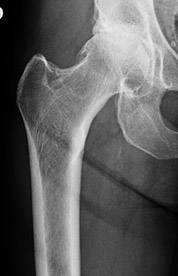

Οστεοαρθρίτιδα του ισχίου είναι η διαρκώς επιδεινούμενη φθορά κι εκφύλιση της άρθρωσης με αποτέλεσμα την πλήρη καταστροφή της. Εμφανίζεται σε άνδρες και γυναίκες συνήθως μετά το 60ο έτος ηλικίας προκαλώντας έντονο πόνο, μεγάλη δυσχέρεια στην κίνηση και βάδιση και δραματική επίδραση στην ποιότητα ζωής των ασθενών.

Εμφανίζει μεγάλη αύξηση στη συχνότητα της στο γενικό πληθυσμό λόγω της αύξησης του μέσου όρου ζωής αλλά και της ενασχόλησης όλο και μεγαλύτερων ανθρώπων με τα σπόρ.